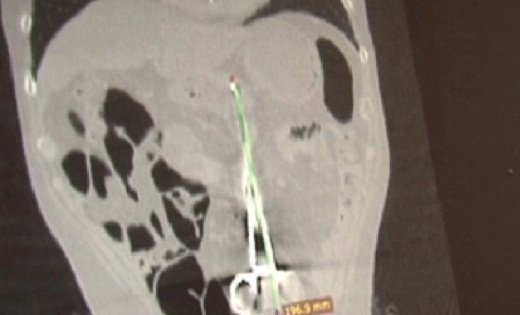

После этого Машау повела своего супруга на томографию. Во время процедуры ему стало плохо, случился аллергический шок, дедушку едва удалось спасти. Почти через месяц пришли результаты томографии Бектура Жумановича, которые шокировали не только врачей, но и всех родственников. Оказалось, что в животе у него находится инородное тело – хирургический зажим. Врачи просили не афишировать эту информацию.

"Я сказала: "Нет-нет, я ничего говорить не буду, лишь бы его спасли! Помогите ему!". 11 декабря его привезли в больницу Шахтинска. Сделали рентген. А на снимке большущие ножницы! Прямо страшно стало. Стали готовить к операции. Сказали, что она много времени не займет. На другой день с девяти до трех часов шла операция. Врачи сказали, что у него все кишки как клубок сделались, обернулись вокруг зажима. Я уже думала, что потеряла мужа. Потому что из-за больного сердца ему нельзя было делать наркоз", - рассказывает Машау.